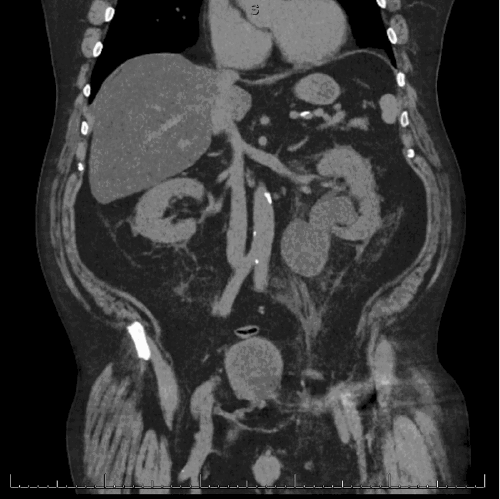

Figure 1. Preoperative CT Imaging of Ureteral Inguinal Hernia. Published with Permission

Coronal view demonstrating severe left-sided hydronephrosis and hydroureter proximal to the point of herniation

Axial view showing the incarcerated and hydronephrotic distal left ureter contained within the left inguinal hernia sac